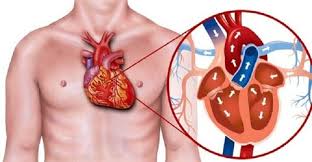

قیمت: 88٬000 تومان - دسته بندی فایل: تحقیقپاورپوینت کنترل بیماری های قلبی عروقی (ppt) 68 اسلاید

فروش ویژه فایل های پاورپوینت کنترل بیماری های قلبی عروقی با تخفیف استثنایی - دسته بندی: پاورپوینت نوع فایل: PowerPoint (pptx) (قابل ویرایش و آماده پرینت) تعداد اسلاید: 68 اسلاید

قیمت: 54٬000 تومان - دسته بندی فایل: تحقیقپاورپوینت بررسی بیماری پریکاردیت (ppt) 29 اسلاید

فروش ویژه فایل های پاورپوینت بررسی بیماری پریکاردیت با تخفیف استثنایی - دسته بندی: پاورپوینت نوع فایل: PowerPoint (pptx) (قابل ویرایش و آماده پرینت) تعداد اسلاید: 29 اسلاید

قیمت: 54٬000 تومان - دسته بندی فایل: تحقیقپاورپوینت بررسی افتادگی دریچه میترال (ppt) 27 اسلاید

فروش ویژه فایل های پاورپوینت بررسی افتادگی دریچه میترال با تخفیف استثنایی - دسته بندی: پاورپوینت نوع فایل: PowerPoint (pptx) (قابل ویرایش و آماده پرینت) تعداد اسلاید: 27 اسلاید